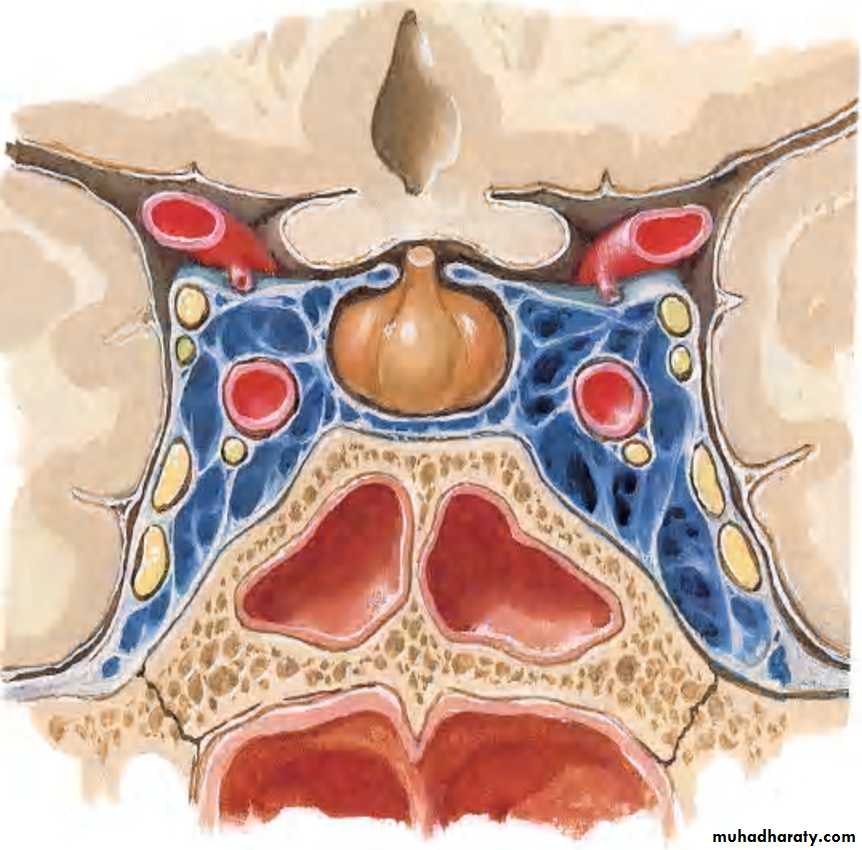

SPHENOIDAL SINUS:

Resides in body of sphenoidMay be single or paired

Asymmetrical

Unequal in size

RELATIONS:

1.Cavernous sinus lies laterally containing the:

• IIIrd,• IVth,

• Vth (ophthalmic

and maxillary-

divisions) and

• VIth cranial nerves,

2.Internal carotid artery

SUPERIORLYOptic chiasma

Hypophysis cerebri